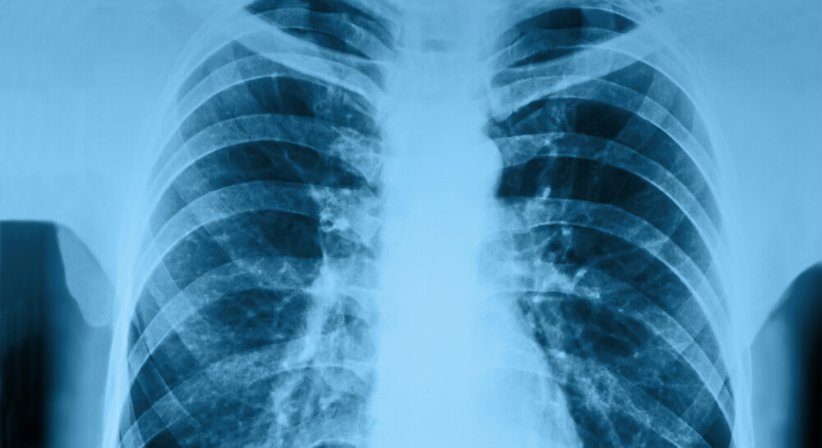

· Auffälligkeiten im Lungenröntgen aufweisen